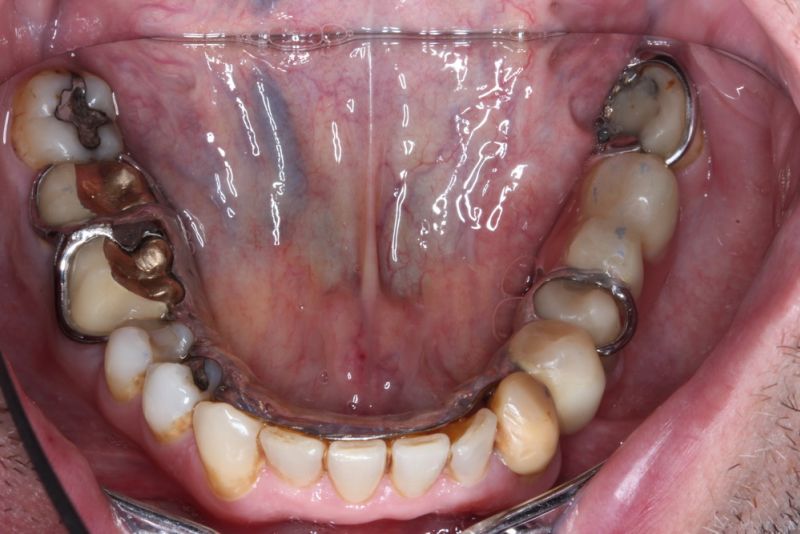

Der Patient hat von einem CMD Spezialisten in Bielefeld einen Aufbissbehelf erhalten. Den hat der Patient mit Zellstoff unterfüttert, weil der Aufbissbehelf so unterschiedlich hoch war, dass der Patient es vor Schmerzen mit dem Aufbissbehelf nicht ausgehalten hat.

2. Herstellung und Eingliederung eines adjustierten Aufbissbshelfs

Erkennbar ist die massive Abweichung der habituellen Bisslage von der neuromuskulär zentrierten Bisslage.